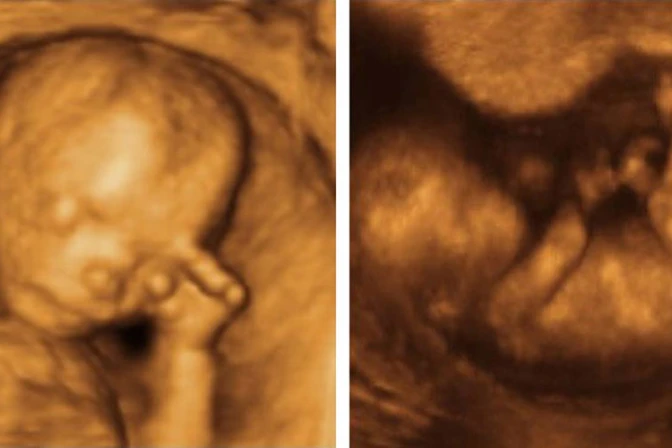

El proyecto HB90, conocido como de "Humanidad del niño por nacer" permitiría que el directorio de educación y el departamento de salud del estado de Ohio generen un currículo escolar que "proporcione información precisa y científicamente verificable sobre las características anatómicas y fisiológicas del niño por nacer" durante el embarazo.

El proyecto ha sido presentado por el republicano Niraj Antani, quien dijo al diario Columbus Dispatch que "cuando aprender que el corazón de un bebé late a las seis u ocho semanas, que las uñas se forman a las 10 semanas, y que a las 20 se siente dolor, todo eso sin duda ayudará a crear una cultura de vida".

Los que apoyan la norma afirman que educar a los niños y adolescentes sobre el desarrollo fetal y la salud durante el embarazo, es algo bueno para las madres y sus bebés.